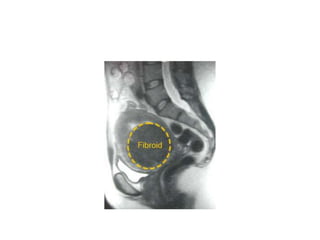

PATHOLOGY

• May reach 15 cm in size or larger